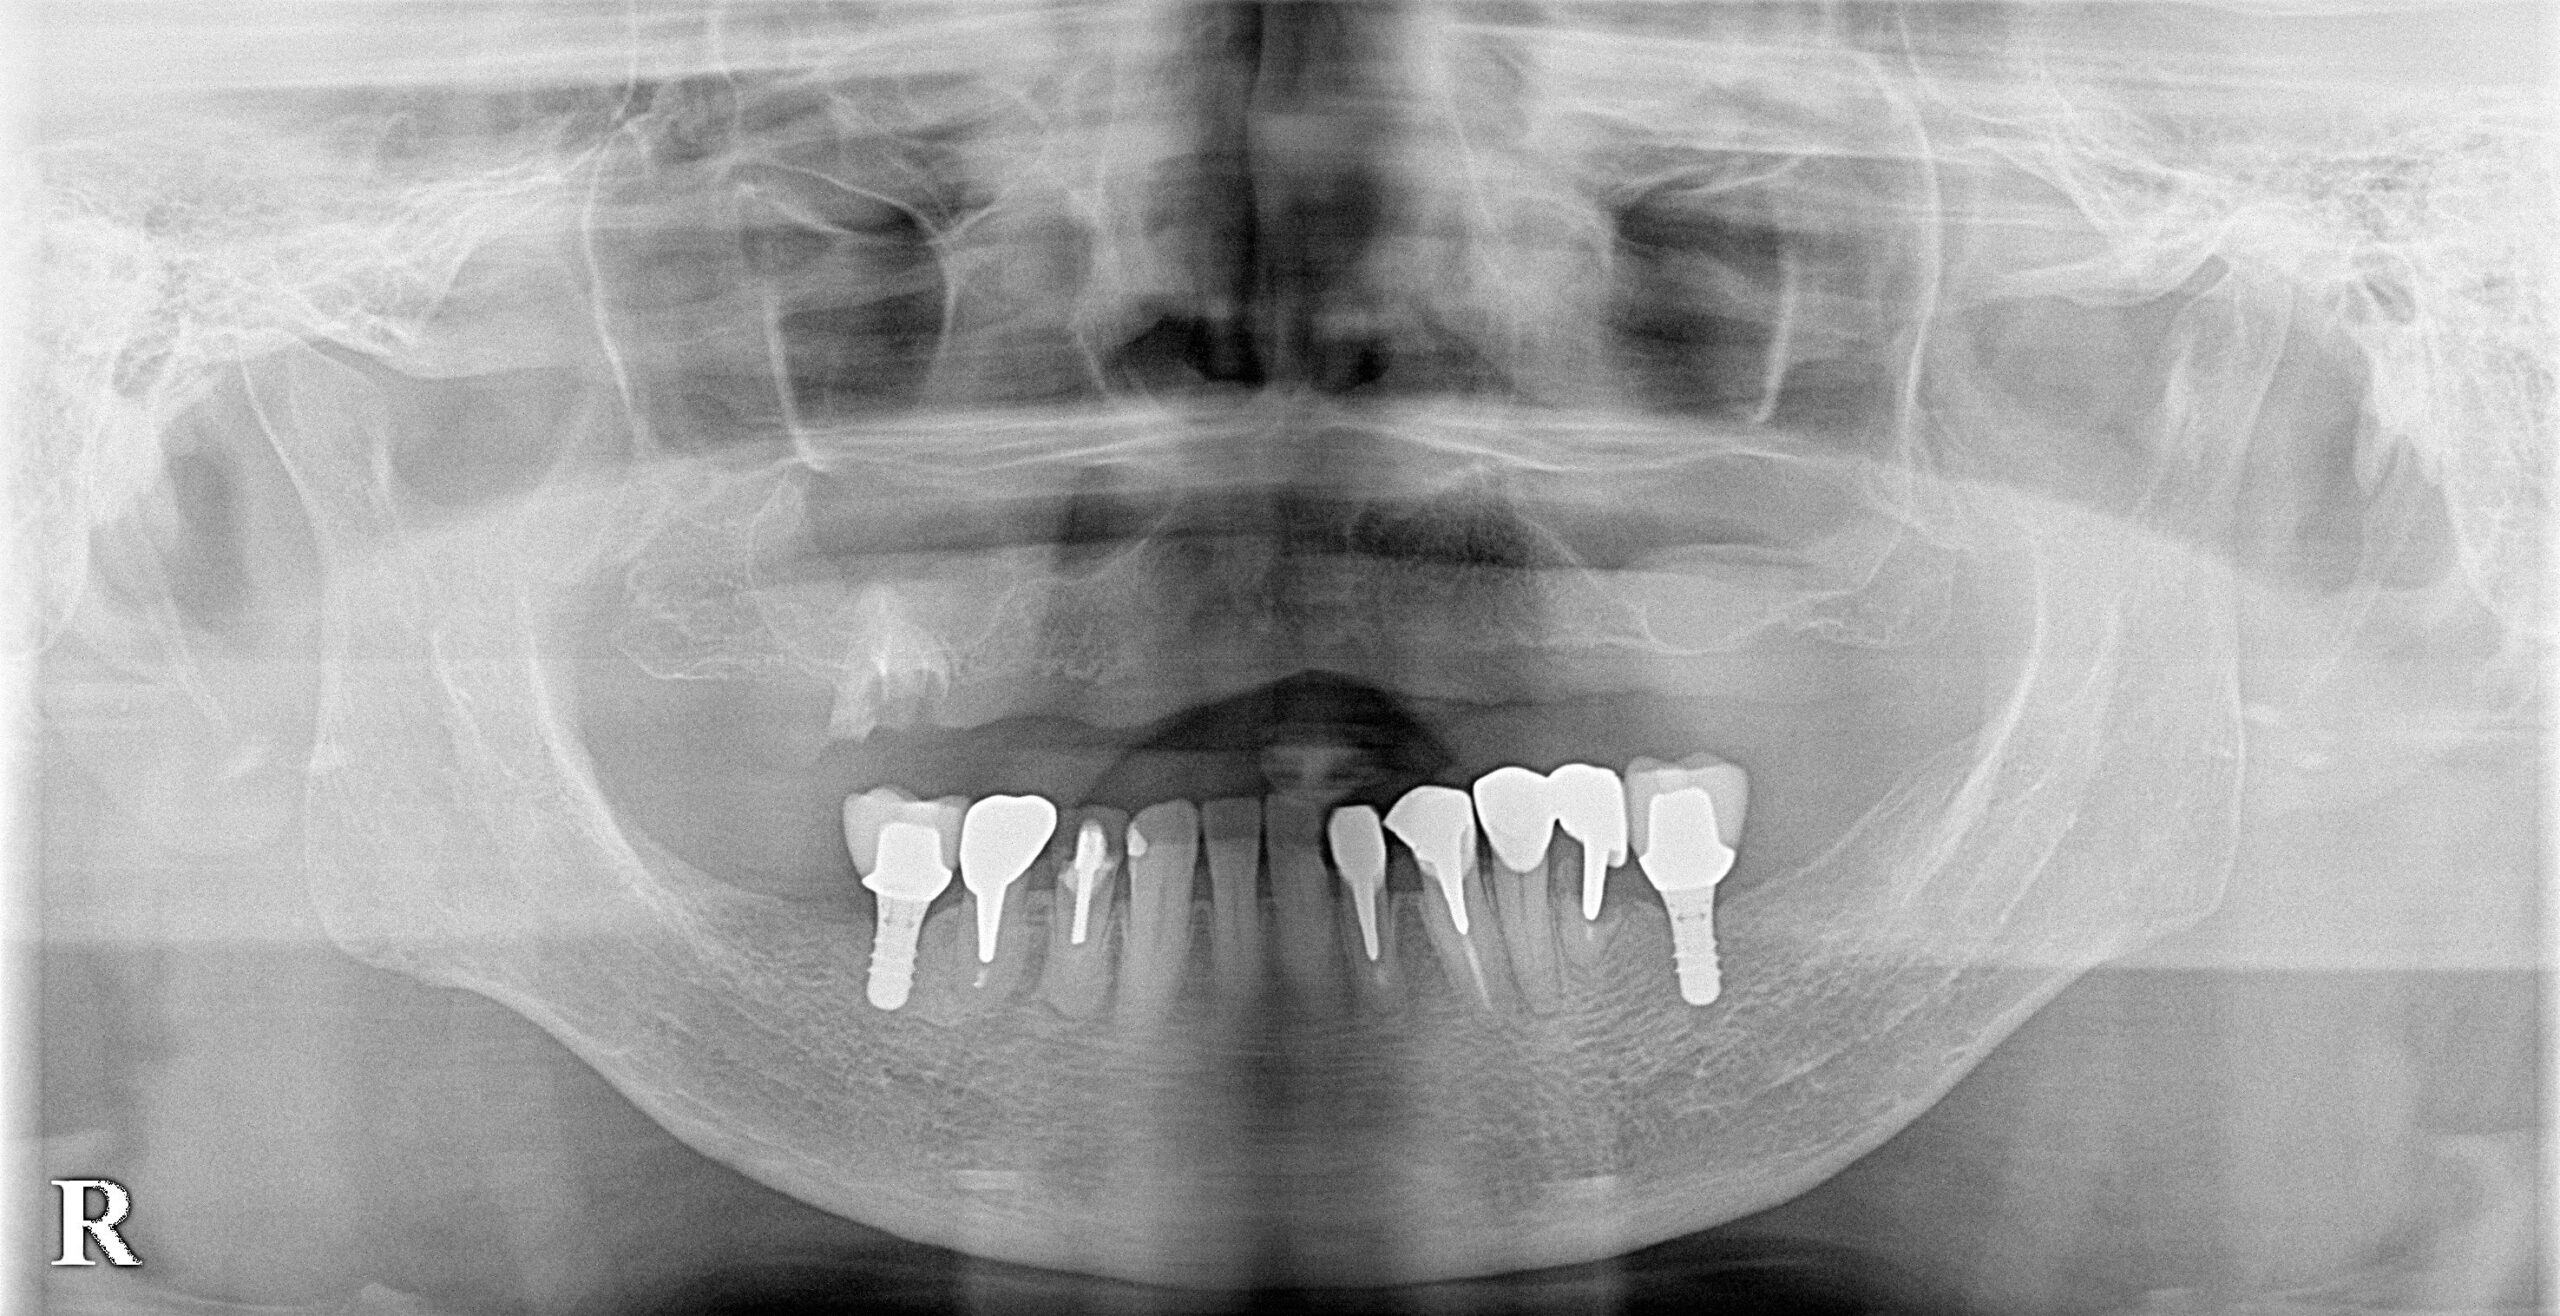

60代女性 AGC(全顎インプラント)

- AGC(全顎インプラント)治療

- 入れ歯を卒業したいと、全顎的なインプラント治療を決意されました。

- 特殊な「AGC構造」で作られるインプラントブリッジは、ネジも接着剤も使わず高精度の嵌合で固定されます。この患者様は6本で連結されており、簡単には外れませんが、専用器具で着脱可能です。丸洗いできるため衛生的で、将来的に介護が必要な場合も対応しやすいなどの特徴があります。